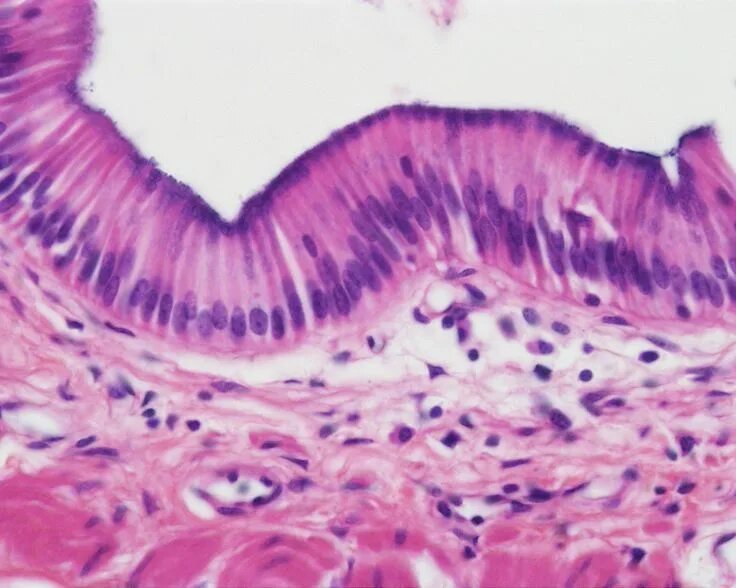

Ткань бывает реснитчатой